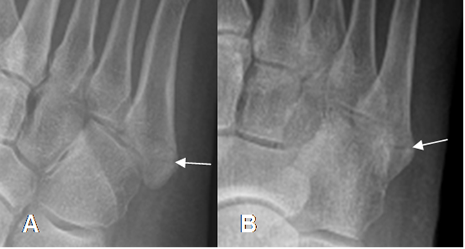

Fig 52 A. Avulsión del 5º metatarsiano.

A: Rx oblicua y B: Rx AP. Fractura no desplazada en la base del 5º metatarsiano, por avulsión no desplazada.

Fig 52 B. Avulsión del 5º metatarsiano.

A: Rx AP y B: RX oblicua. Fractura desplazada y con compromiso intra-articular, en la base del 5º metatarsiano, por avulsión desplazada.